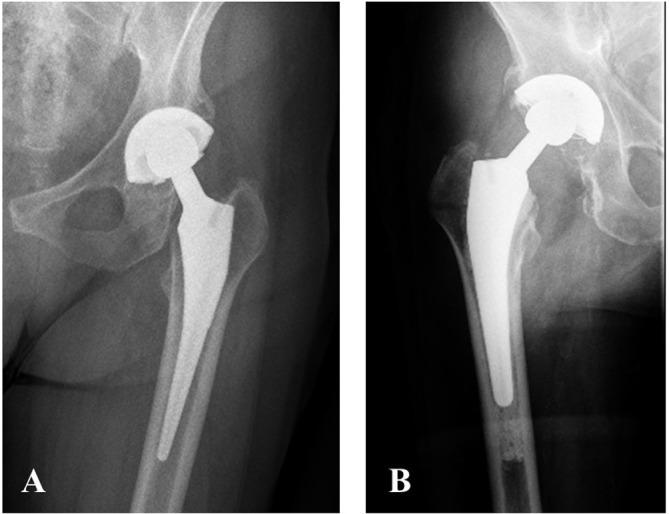

The medical records of 71 patients (76 hips), operated on between January 1991 and December 2003, who had a minimum follow-up of 10 years were available for analysis. Functional analysis was performed with the Harris hip score (HHS) questionnaire and the numerical analogue scale (NAS). Radiographic analysis was performed for subsidence, radiolucent lines and osteolysis.

The cohort was comprised of 47 female and 24 male patients, with a mean age of 59.7 ± 12.4 years. The mean follow-up was 17.8 ± 4.4 years. 52.6% of THAs analyzed were cementless and 47.4% were cemented. Post-operative radiographs were available for 57 surgeries. Subsidence, hypertrophic ossification, radiolucent lines and osteolysis were noted in 4 (7%), 2 (2.6%), 14 (18.4%) and 11 (14.5%) hips respectively. The average HHS score at a mean follow-up of 20.1 ± 3.9 years was 62.1 (±27.7) and the NAS score was 4.6 (±3.6). During the study period, five revision surgeries were performed due to stem-related problems, one of which was for aseptic loosening.

Our long-term experience with the Taperloc stem, both cemented and cementless, demonstrates good outcomes, with low rates of failure. This makes this prosthesis an attractive option for THAs.